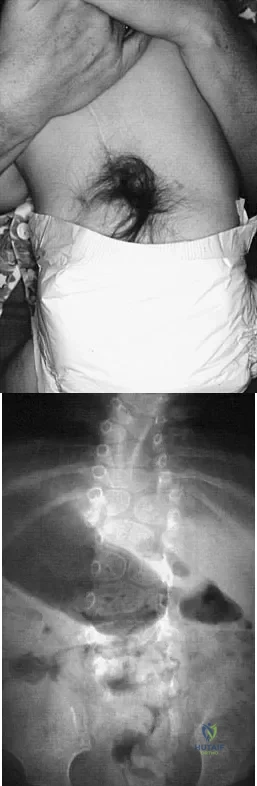

A 4-month-old infant is referred for evaluation of congenital scoliosis. The child has no congenital heart anomalies, and a renal ultrasound shows that he has one kidney. Examination reveals mild scoliosis and a large hairy patch on the child's back. Neurologic evaluation is normal for his age. A clinical photograph and radiograph are shown in Figures 19a and 19b. Initial management should consist of

Explanation